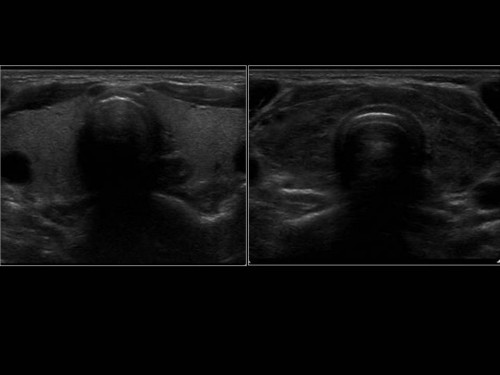

ICD: E06.3